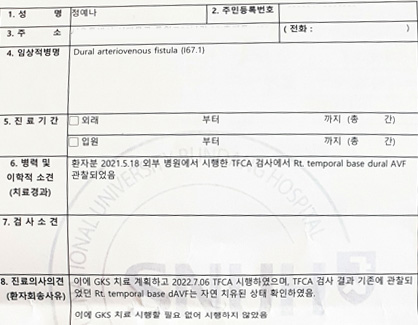

Diagnosis after healing

Ō¢▓ For the patient, Rt. Temporal bas dural AVF was observed. Therefore, GKS treatment was planned and TFCA was performed on July 6, 2022. As a result of the TFCA test, the previously observed Rt. Temporal base dAVF was confirmed to have been healed naturally. Therefore, there was no need to perform GKS treatment, so it was not performed.